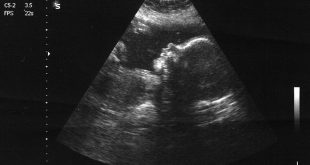

بررسی جدید: ارتباطی میان سونوگرافی دوران بارداری و اوتیسم وجود ندارد

سونوگرافی دوران بارداری

نوروسافاری | پژوهشگران آمریکایی در بررسی اخیر خود اعلام کردند سونوگرافی دوران بارداری ارتباطی با اوتیسم در کودکان ندارد. به گزارش نوروسافاری از ساینتیفیک امریکن، آزمایشات سونوگرافی در دوره بارداری، متداول است و اخیرا، پژوهشگران این موضوع که آیا احتمال وجود اختلال طیف اوتیسم در میان کودکانی که در رحم …